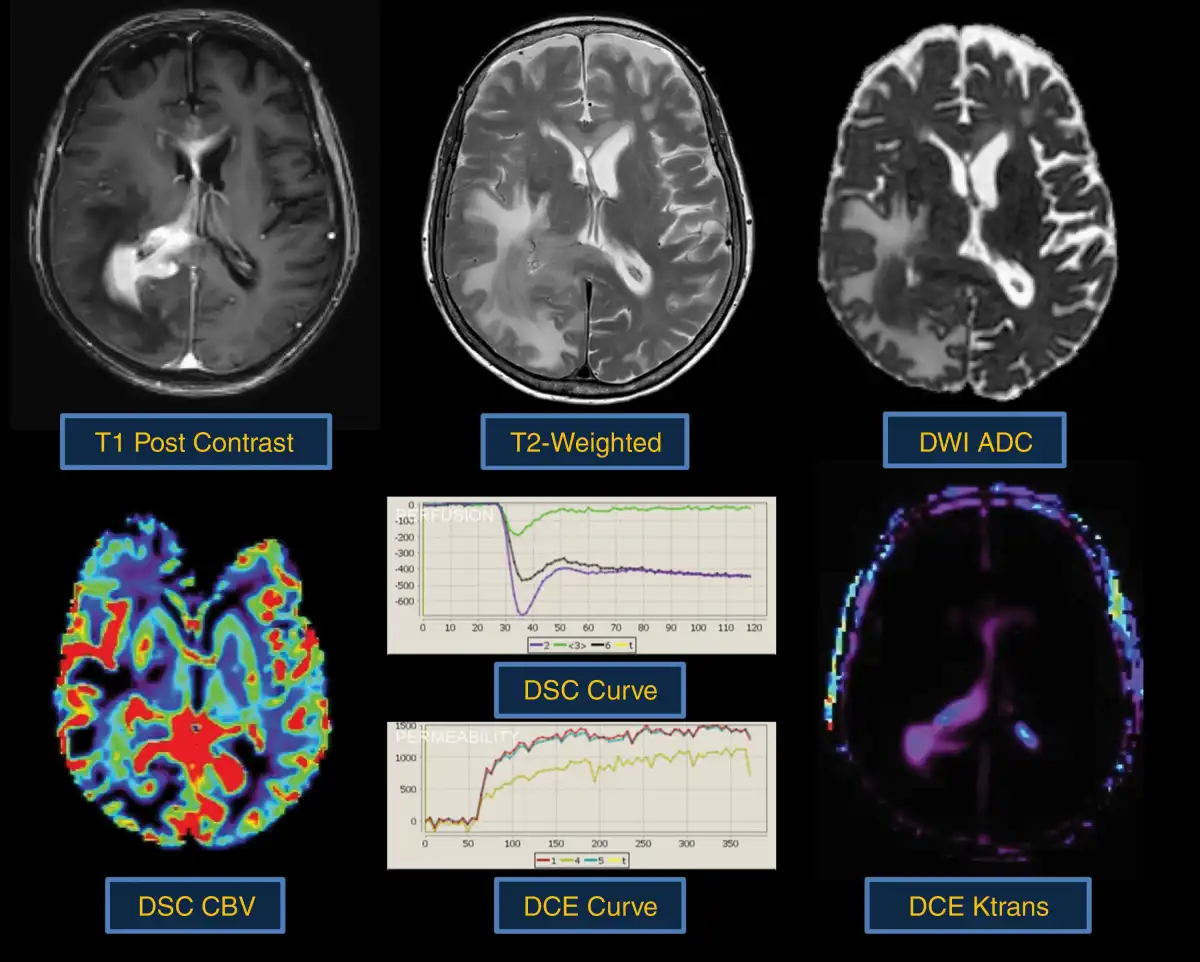

Fig. 1

Biophysical features characterized by conventional and advanced physiologic MRI techniques. Shown are 6 MRI techniques that are commonly employed in neuro-oncologic imaging, along with their respective corresponding tumor phenotypes. T2-weighted (T2W) signal is typically used to define vasogenic edema. T1-weighted post-contrast enhancement (T1 + C) shows areas of disrupted blood-brain barrier (BBB). Dynamic susceptibility contrast (DSC) MRI measures of relative cerebral blood volume (rCBV) define microvascular volume as an indicator of tumor-related angiogenesis. Dynamic contrast-enhanced (DCE) MRI measures of vascular permeability (Ktrans). Diffusion-weighted imaging apparent diffusion coefficient (ADC) correlates with cellular density and proliferative indices and can aid in distinguishing tumor from vasogenic edema. Diffusion tensor imaging (DTI) fractional anisotropy (FA) measures the integrity of white matter tracts, which can be used to identify regions of tumor infiltration.

ADC values are also clinically useful in the differentiation of PCNSL from other primary brain tumors as ADC values within PCNSL are significantly lower when compared to glioblastoma. This suggests that the high degrees of cellularity can be useful in the diagnostic assessment of PCNSL (Figure 3). Additionally, the combined diagnostic performance of PCNSL CSF biomarkers (CXCL-13 and IL-10) and ADC is superior to the use of any single biomarker.

Typical morphologic and physiologic MRI appearance of PCNSL. PCNSL classically appears as a diffuse often periventricular enhancing mass (top left). T2-weighted imaging is often heterogenous but frequently demonstrates a mass like hypointense component (top middle) within enhancing regions. Increasing tumor cellularity is associated with decreasing T2 and ADC hypointensity (top right). Likewise, the degree of angiogenesis is reflected by DSC and DCE perfusion MRI sequences. CBV (bottom left) and Ktrans (bottom right) are quite heterogenous in PCNSL and may be reflective of tumor aggressiveness.

Dynamic susceptibility contrast perfusion MRI.—Over the past decade, DSC-MRI emerged as a clinically valuable and accessible tool in neuro-oncology. The DSC-MRI technique measures relative cerebral blood volume (rCBV) as a surrogate noninvasive imaging biomarker of tissue microvascular volume., rCBV assessment may be of clinical utility for PCNSL diagnosis and clinical outcomes., The observation that rCBV may be of predictive value is consistent with the reported histological observations. Takeuchi et al. have demonstrated that patients with lymphoma with elevated vascular endothelial growth factor (VEGF) expression and microvascular density counts had prolonged OS. Future studies are needed to apply rCBV for other potential applications, including characterization of disease burden, molecular stratification, and contribution to response assessment.

Assessment of rCBV has also been shown to be clinically useful in the pre-operative differentiation of PCNSL from glioblastoma. The literature suggests that PCNSL rCBV values, while somewhat variable, nonetheless are lower than those observed within glioblastoma (Figure 3). This difference may aid in the clinical diagnosis of PCNSL and suggests that a fundamentally distinct biological process is occurring. Unlike glioblastoma, PCNSL neoangiogenesis does not result in marked degrees of microvascular proliferation or microvascular glomeruloid dilation. Histological and electron microscopy of PCNSL microvasculature suggests that only a minority of tumors demonstrate neoangiogenesis that lacks a neurovascular unit.

Dynamic contrast-enhanced (DCE) perfusion MRI.—DCE-MRI captures unique features of the vascular microenvironment including BBB permeability, making it a candidate to characterize lymphomas and other brain tumors, in the differential diagnosis, response assessment, and survival analysis., A study by Ferreri and colleagues demonstrated Ktrans as a useful biomarker to measure changes in BBB permeability of the vasculature and perilesional area in lymphoma before and after the injection of a permeabilizing agent. Among all DCE-MRI parameters, Ktrans is most consistently demonstrated its value in distinguishing differential diagnoses. The finding of higher values of Ktrans in lymphoma when compared to other brain lesions like glioblastoma and metastases has been confirmed in several independent studies, and is consistent with the findings of other imaging modalities that are able to assess vascular permeability, like CT (computed tomography) perfusion and DSC-MRI., In addition to Ktrans, the extracellular volume fraction, termed “Ve,” may differentiate lymphomas from other brain tumors; however, the true physiological interpretation is still debated. Ve is defined as the volume of the extravascular extracellular space and is thought to correlate with tumor cellularity. Ve is consistently been found to be higher in lymphoma than in glioblastoma and brain metastases, suggesting that this parameter may provide unique information about the tumor microenvironment and not specifically tumor cellularity.